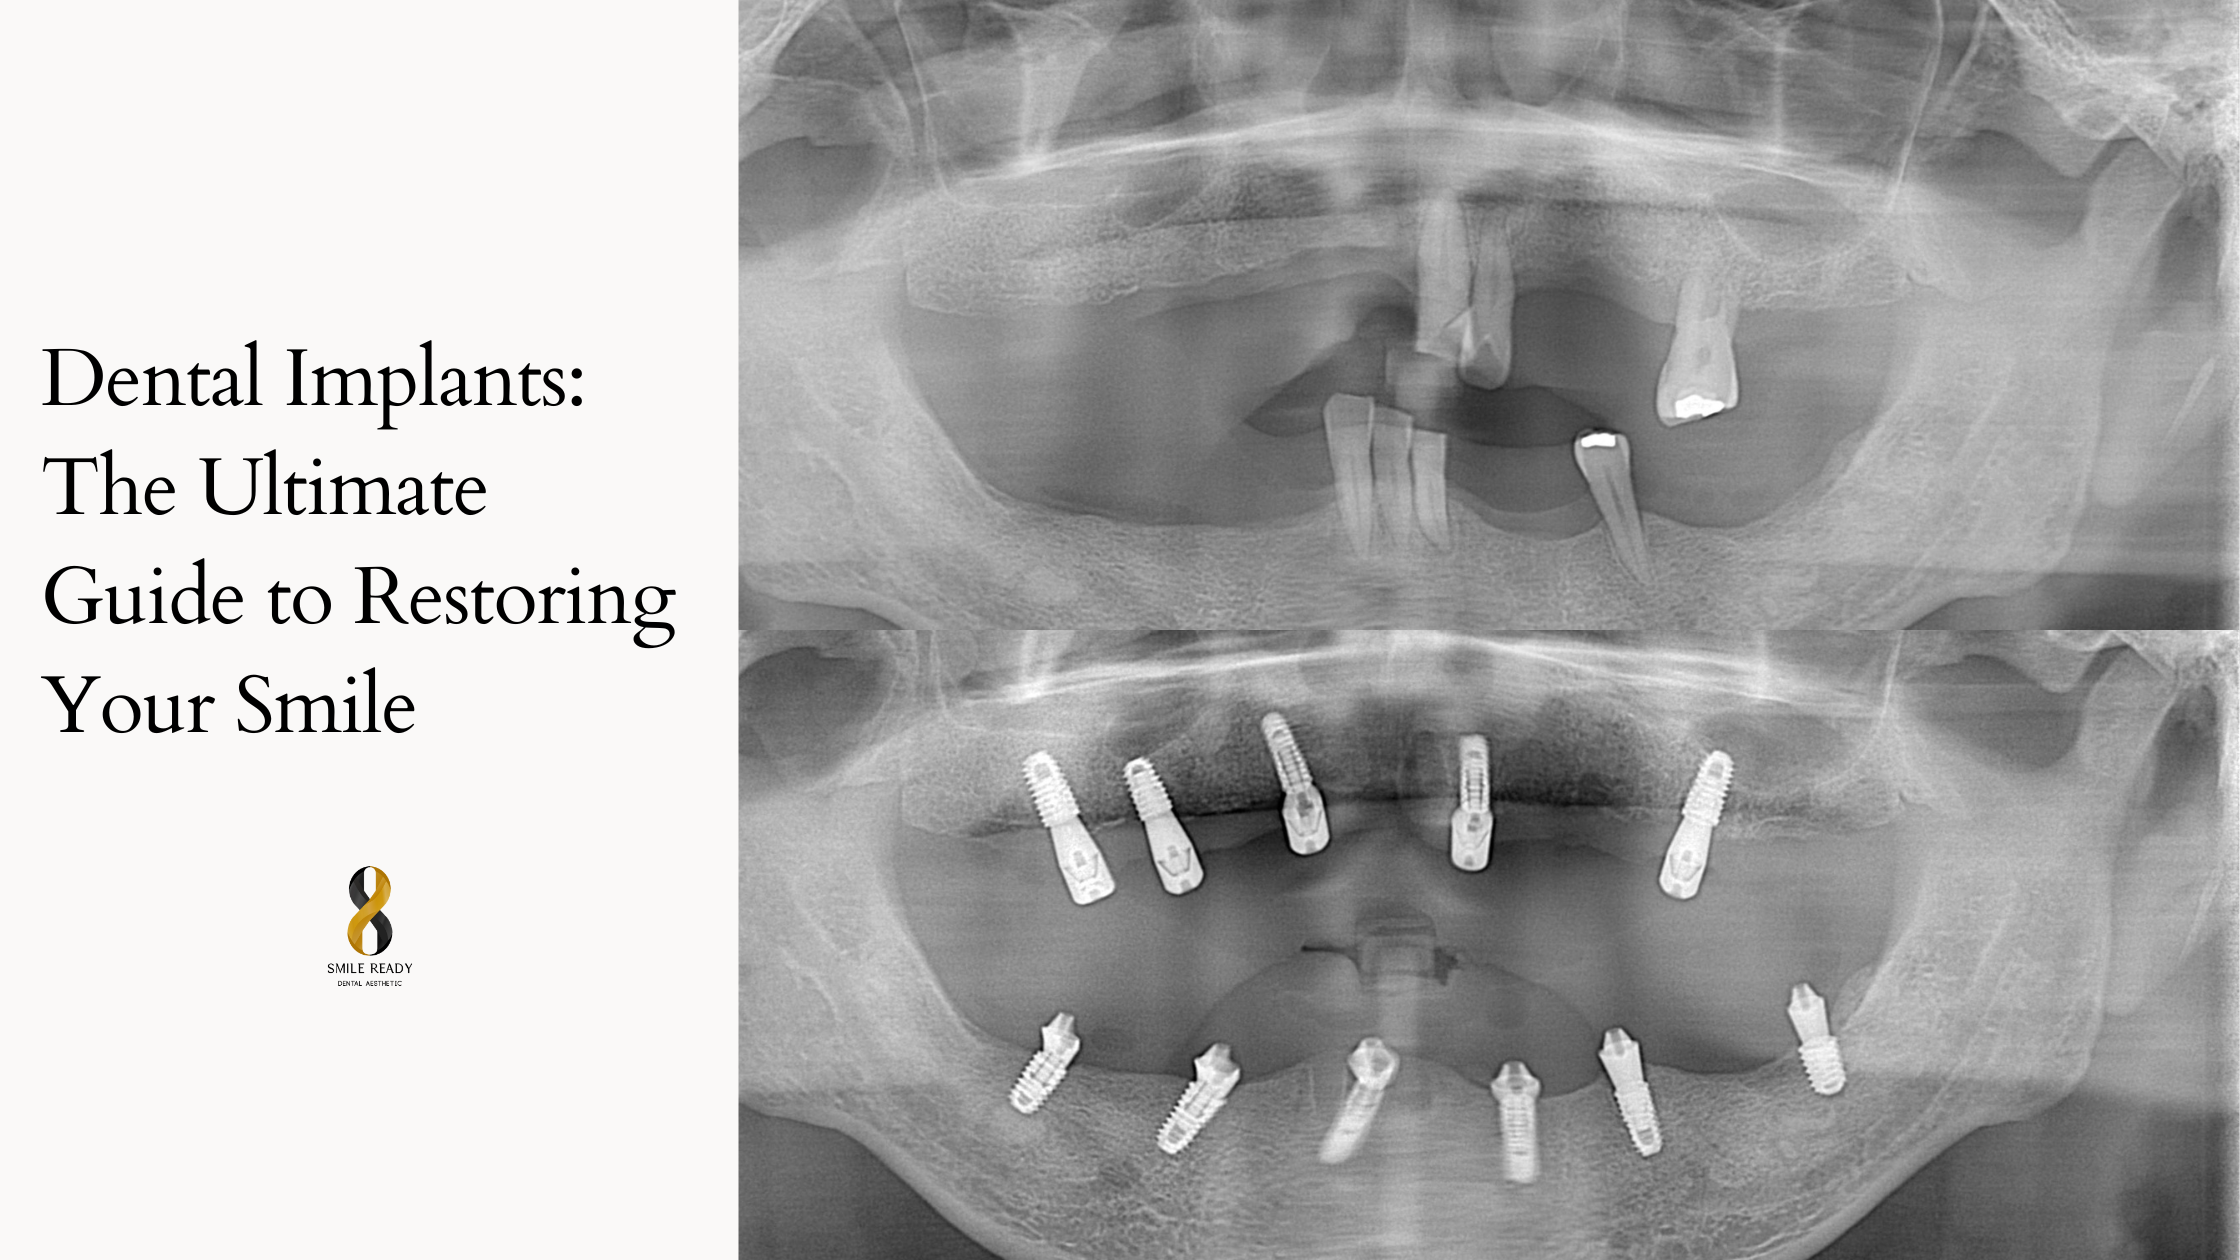

Advanced guided implant surgery uses 3D imaging like CBCT scans to map precise placement, minimizing errors and speeding healing. Immediate load implants allow temporary restorations on the same day for suitable candidates with dense bone, cutting overall timelines. Full procedures span 4-9 months, including healing phases, but deliver results lasting decades with proper care.

All-on-4 and All-on-6 systems revolutionized full mouth dental implants, supporting entire sets of teeth on fewer posts, ideal for those avoiding extensive grafting. Mini implants provide quick, less invasive options for temporary fixes or overdentures.